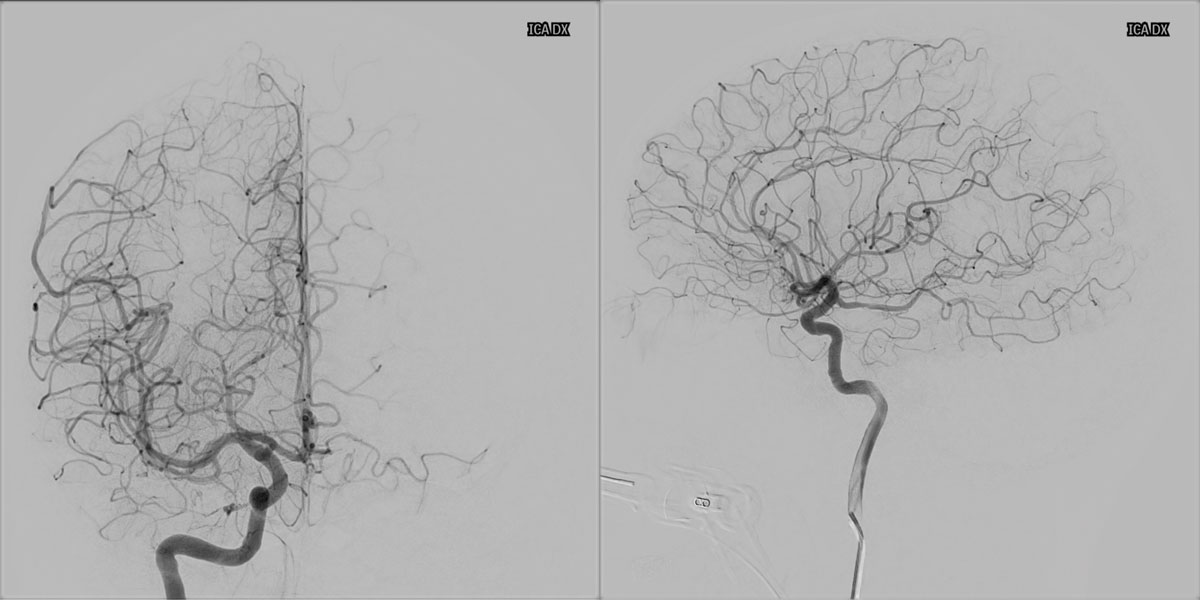

6 months DSA follow up